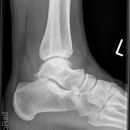

Snowboard fracture Talus